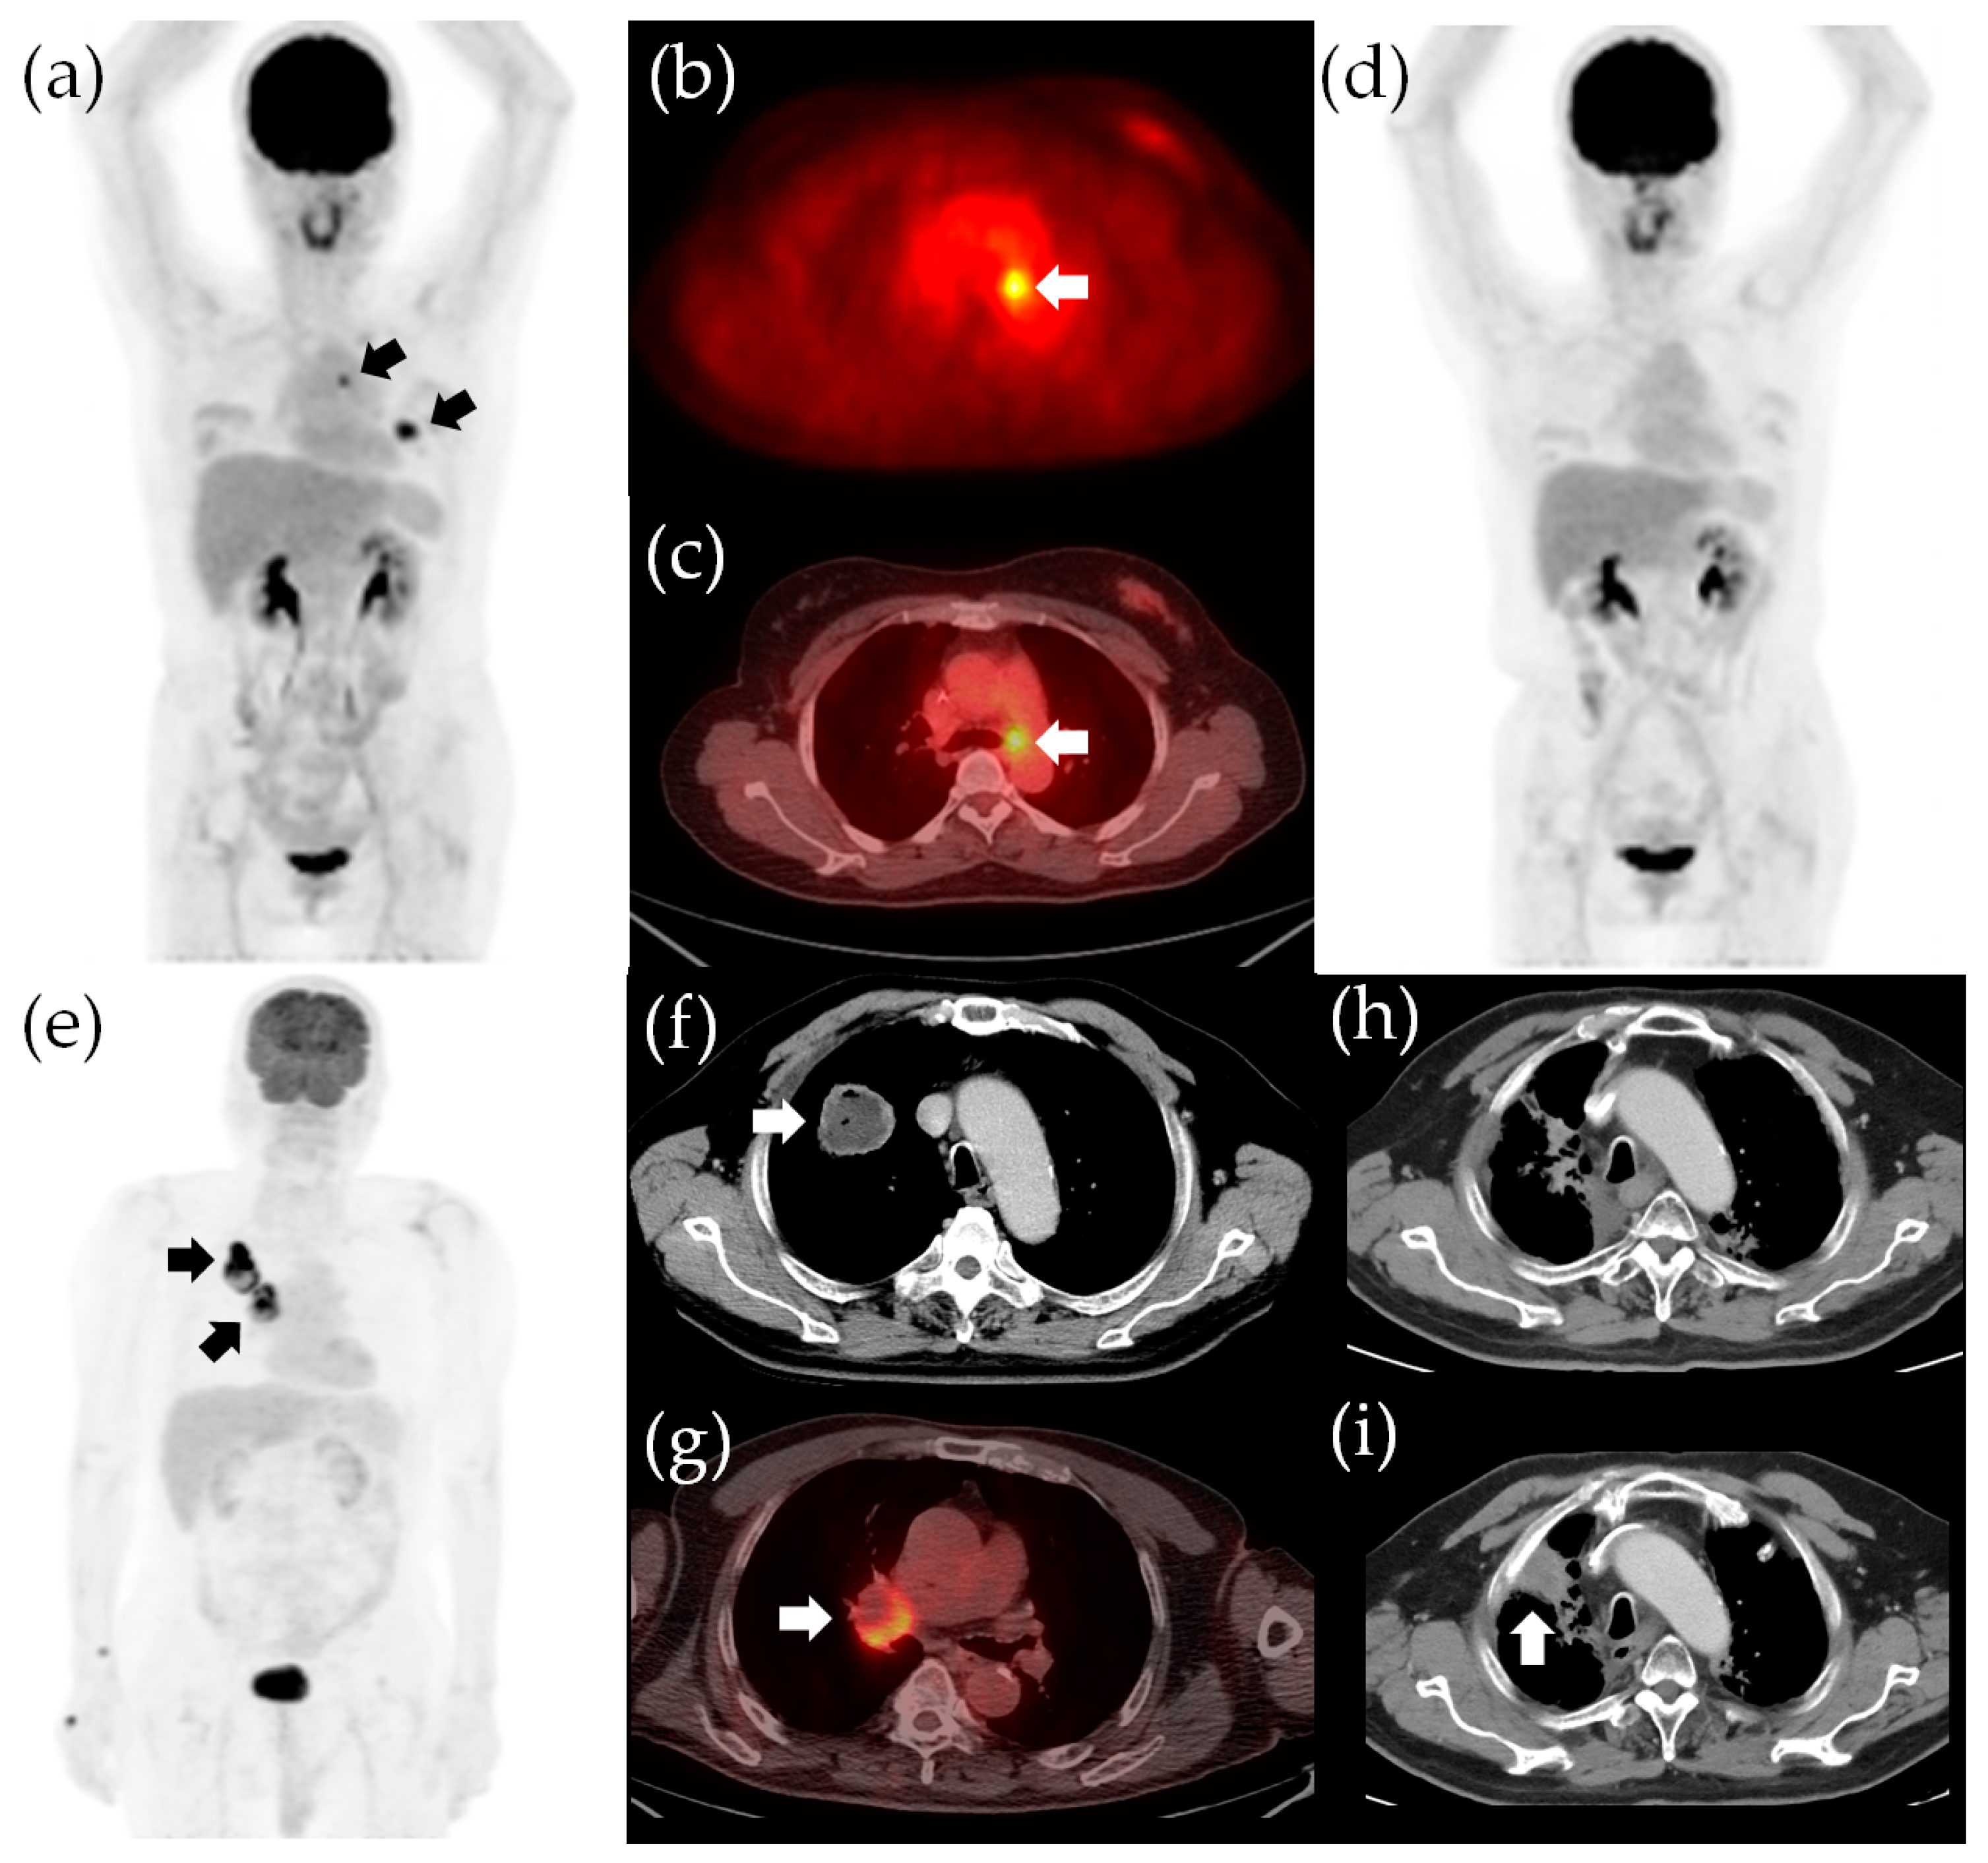

In our study, the total TLG is an independent risk factor depicting the disease, while the age and ECOG status characterize the host vitality. Survival outcomes in patients with cancer result from the complex interplay between the tumor and the host. Robust patient conditions with limited total TLG would have a higher chance of attaining disease-free status after curative treatment. On the other hand, vulnerable patient status and sizable total TLG are likely to experience treatment failure and eventually succumb to recurrence or disease progression (Figure 4). Therefore, incorporating both disease and host factors into one survival prediction model refines the prognostic stratification. Our survival stratification models also showed predictive value for survival outcomes in subgroups receiving different initial treatments. Because therapeutic decisions may vary from patient-to-patient based on clinical factors such as age, the baseline survival risk in subgroups receiving different initial treatment may vary as well [9,46]. For example, patients receiving curative surgery tend to be younger; thus, the surgical group has a lower baseline survival risk according to age. Nevertheless, the results of our study showed that our survival prediction model could be applied to different subgroups receiving different initial treatments, suggesting a wide utility of our survival stratification models in different treatment scenarios.

Figure 4.

Survival stratification according to the independent risk factors in our study. The 18F-FDG PET/CT images for a 50-year-old woman with adenocarcinoma in the left upper lobe and subaortic nodal metastasis, indicated by arrows in the panels (a–c). The clinical staging was cT2aN2M0, stage IIIA. The total TLG was 14.9 and the ECOG status was 0. The patient had no poor survival risk factor (hazards were both 1 for an unfavorable OS and poor PFS) and she underwent lobectomy of the left upper lobe and mediastinal lymph node dissection. The pathological staging was pT2aN2M0, stage IIIA. She underwent adjuvant chemotherapy and is now alive without recurrence (d). The OS and PFS were 116 and 115 months, respectively. A 75-year-old man with adenocarcinoma in the right lower lobe and ipsilateral hilar nodal metastasis, indicated by arrows in the panels (e–g). The clinical staging was cT2bN1M0, stage IIB. The total TLG was 246.6 (>81) and the ECOG status was 1 (the hazards for unfavorable OS and poor PFS were 16.8 and 3.3, respectively). The patient received definitive CCRT (2 Gy/fraction daily to a targeted dose of 66 Gy) and marked tumor shrinkage was observed (h). However, the patient experienced progression of the primary tumor 15.9 months after definitive CCRT, indicated by the arrow in the panel (i). The patient eventually died of lung cancer progression, with an OS of 24.0 months and PFS of 15.9 months. TLG, total lesion glycolysis; OS, overall survival; PFS, progression-free survival; CCRT, concurrent chemoradiotherapy.